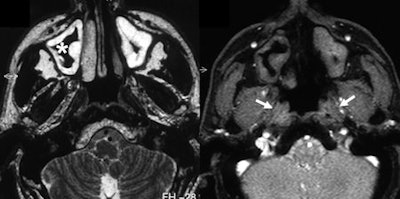

The T2-weighted image shows carcinoma in the left recess of Rosenmüller (arrows). The eustachian tube is not infiltrated, but slightly displaced laterally. All images courtesy of Dr. Gabriele Krombach.

T2-weighting shows sinusitis with swelling of the mucosa. Real-time imaging demonstrates that both eustachian tubes do not open during Valsalva maneuver (right image, arrows).It was possible to evaluate the opening of the eustachian tube during the Valsalva maneuver in all patients. Within the same examination, an underlying problem was identified and its extent delineated in 14 of the 16 patients. In all patients, the anatomical landmarks and structures were clearly depicted and differentiated from pathological abnormalities in the T2-weighted sequence. Involvement of the anatomical structures could be assessed, but the osseous part of auditory tube was depicted with less good image quality than the other parts. In this region, the amount of soft tissue is small and consists only of the mucous membrane, connective tissue, and the periosteum.